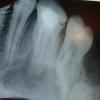

Иван. Опубликовано 12 января, 2011 Поделиться Опубликовано 12 января, 2011 (изменено) добрый день Мальчику 12 лет, жалобы на 16 зубик, пролеченный три года назад, реакция на холод, боль ноющая 2 дня, ну вроде бы все ясно (по снимку). Обострение и боль удалось снять за день (полоскания, компрессы, диета), но я все же посчитал необходимым показать мальчика его стоматологу для полного спокойствия. Не думал, что она будет вскрывать канал. Результат лечения зуба на снимках до и после. Вопроса всего три:1. А нужно ли было вскрывать к.к., если положительная динамика наблюдалась 3-й день?2. Перелечивать к.к. теперь однозначно необходимо? - стоматолог против3. Стоматолога менять? - у меня возможности пока нет самому вести прием. Изменено 12 января, 2011 пользователем Иван. Ссылка на комментарий

koss Опубликовано 12 января, 2011 Поделиться Опубликовано 12 января, 2011 добрый день Мальчику 12 лет, жалобы на 16 зубик, пролеченный три года назад, реакция на холод, боль ноющая 2 дня, ну вроде бы все ясно (по снимку). Обострение и боль удалось снять за день (полоскания, компрессы, диета), но я все же посчитал необходимым показать мальчика его стоматологу для полного спокойствия. Не думал, что она будет вскрывать канал. Результат лечения зуба на снимках до и после. Вопроса всего три:1. А нужно ли было вскрывать к.к., если положительная динамика наблюдалась 3-й день?2. Перелечивать к.к. теперь однозначно необходимо? - стоматолог против3. Стоматолога менять? - у меня возможности пока нет самому вести прием. 1, нуно однзначно2,да . всё в переделку нёбный апекс или раздолбали или не сформировался ( гадать не буду ) , апекс надо было МТА закрыть3, вам решать раз вопросы задаете Ссылка на комментарий

zybnaya feya Опубликовано 12 января, 2011 Поделиться Опубликовано 12 января, 2011 1. А нужно ли было вскрывать к.к., если положительная динамика наблюдалась 3-й день?2. Перелечивать к.к. теперь однозначно необходимо? - стоматолог против3. Стоматолога менять? - у меня возможности пока нет самому вести прием.Перелечивать однозначно нужно и при этом все четыре.Менять стоматолога тоже желательно Ссылка на комментарий

x3m Опубликовано 13 января, 2011 Поделиться Опубликовано 13 января, 2011 (изменено) вот не хотелось встревать в околонаучную дискуссию, но... По первому снимку выскажите ваше мнение, если бы не воспаление, то что вам не так? да не, ничего. тогда (если бы не воспаление) - все нормально.просто по первому снимку есть 3 маааленьких нюанса - 1. нет апекса.2. необратимое воспаление (не аппелировать уменьшением симптоматики путем использования "бубна и кадила"(с) по авторской методике).3. осложнения воспаления (они известны). а в качестве ответа на первый вопрос темы - 1. А нужно ли было вскрывать к.к., если положительная динамика наблюдалась 3-й день?- можно было и не вскрывать. а научить мальчонку эвакуировать периодически накапливающийся гной через гайморову пазуху путем обучения методике сильного сморкания очищения сахасрара-чакры мое желание подключать пациентов к участию в своем оздоровленииа пациенты в курсе опытов нетрадициональной медицины над их организмами? - не достаточно просто чистить зубы. Если больной сам пройдет через многодневный курс терапии, включающий правильное питание, физические нагрузки, надлежащий уход за полостью рта и кое-что еще, ключевое слово - "кое-то еще", угадал?то ценить свое здоровье он будет очень долго и возможно это положительно повлияет на его образ жизни. Был опыт, когда у больного не только улучшалось самочувствие, но значительно увеличивалась белизна эмали (без отбеливания), но это было лет 15 назад, тогда я в качестве исключений прибегал к такой терапии.создалось впечатление, что Ваш слоган - "Мы будем вас так лечить, что свое здоровье вы будете ценить всю оставшуюся жизнь". (ключевое слово - "оставшуюся"). вся цитата - copyright by Civinskiyno comments ps. ой, чувствую, залечите Вы нетрадиционно 16-й зубик у 12-летнего мальчика... отдайте его хорошему традиционному эндодонту - он Вам потом спасибо скажет.а нетрадиционно значительно увеличьте-ка ему белизну зубиков ("enlarge your bleaching", тасазать) - у него как раз начинается период гона, и за неотразимую улыбку, тренированное тело, сильный дух и => возрастающее число поклонниц он будет Вам вдвойне благодарен. Изменено 13 января, 2011 пользователем x3m Ссылка на комментарий